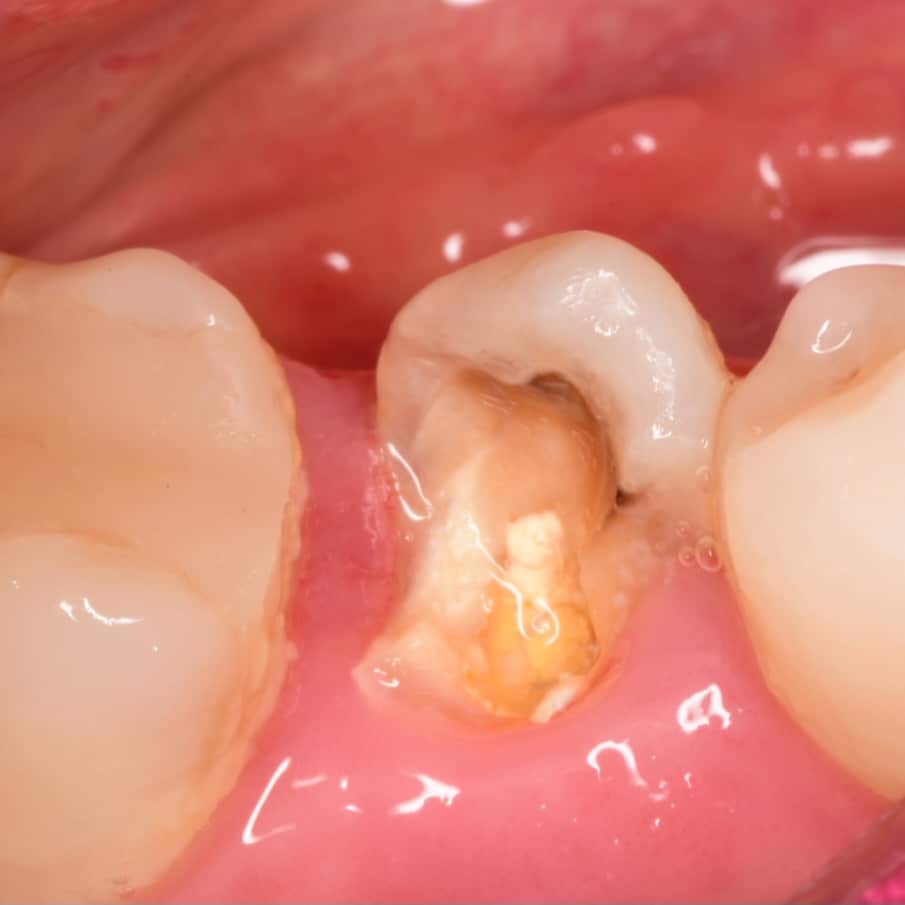

26 years old female patient come to clinic (referred from another dentist )asking for restoring her lower second premolar

Initial situation showing severe decay in lower second premolar